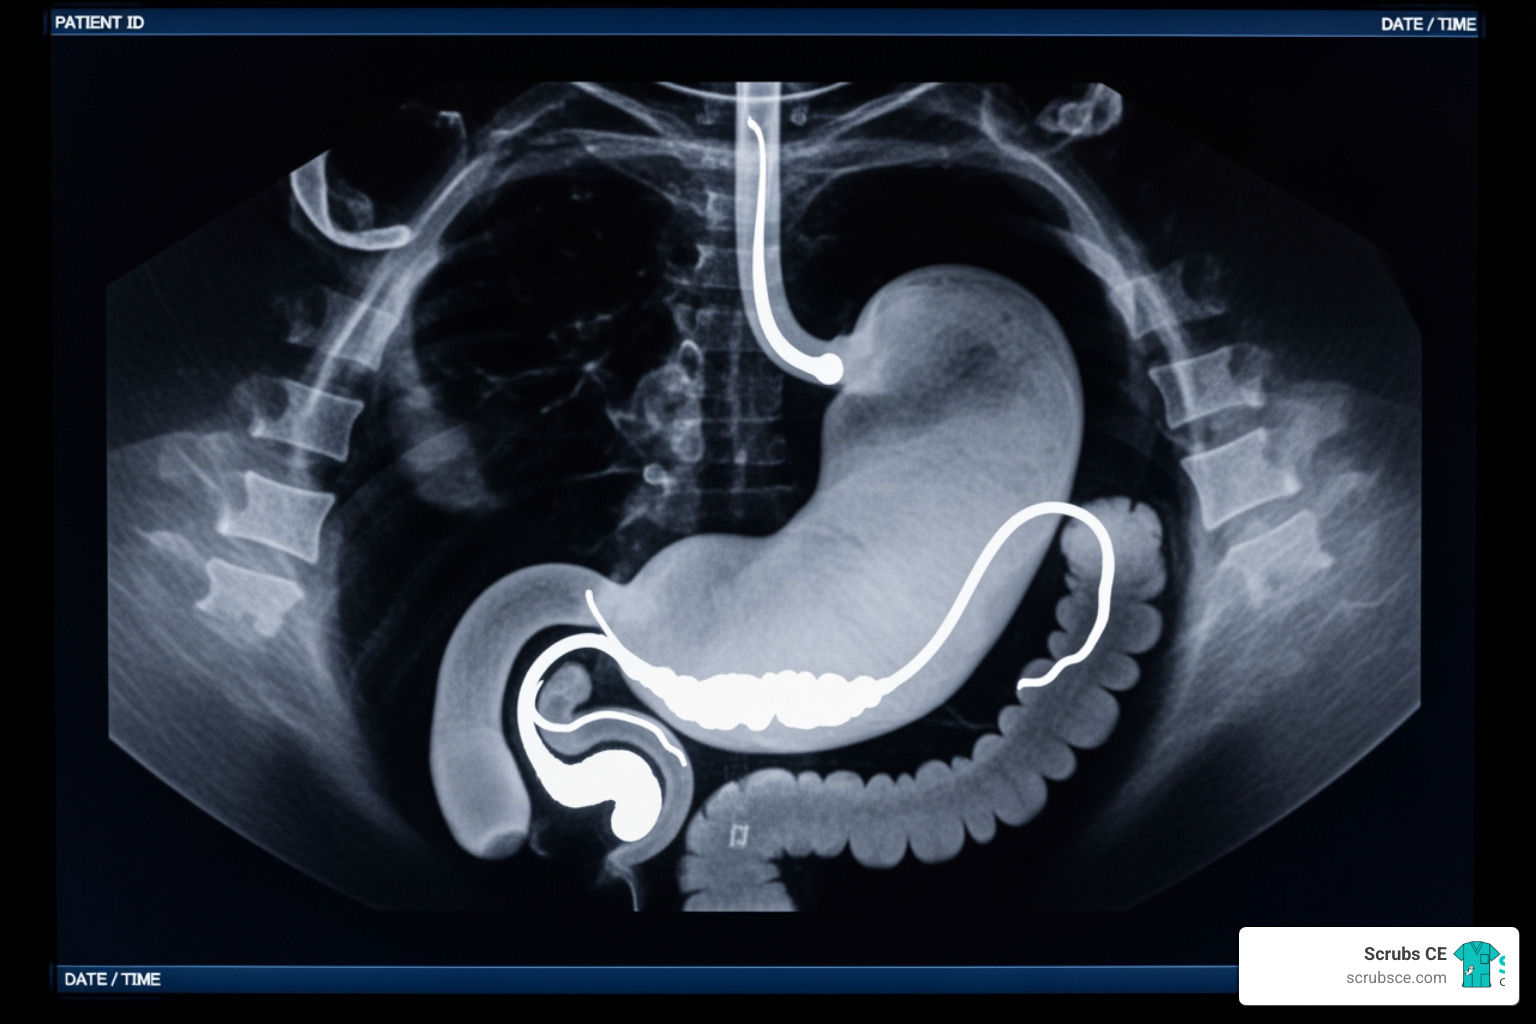

Common imaging modalities employed include fluoroscopic upper gastrointestinal (UGI) series, which are excellent for evaluating the integrity and patency of the new gastrointestinal anatomy, and CT scans, especially with intravenous contrast, for detecting a broader range of complications like abscesses or internal hernias. Ultrasound is often used for gallbladder evaluation, particularly given the increased risk of gallstones after rapid weight loss, and bone density scans (DEXA) monitor for potential changes in bone mineral density.

The effectiveness of these modalities can vary, particularly for critical complications like anastomotic leaks. While UGI series has a high specificity (100%), its sensitivity for detecting leaks within two days post-op is only around 54%. CT, on the other hand, boasts a pooled sensitivity of 91% and a mean specificity of 99.7% for leak detection. For detecting an anastomotic leak, the comparison is as follows:

- UGI Series: Sensitivity 54%, Specificity 100%

- CT with IV Contrast: Sensitivity 91-95%, Specificity 99.7-100%

This data illustrates why CT is often favored for suspected complications, offering a more comprehensive view.

After bariatric surgery, we’re on the lookout for several potential complications, each with tell-tale imaging signs. Anastomotic leaks are among the most feared, and as we’ve seen, CT with intravenous contrast is a highly sensitive tool for their detection, showing sensitivities between 91-95%. A UGI series, while having a lower sensitivity (around 54%), can still be valuable, especially if marginal radiological evidence of leakage is treated as presumptively positive.

Other complications include staple-line hemorrhage, which often appears as a hematoma on CT. Abscesses, collections of pus, are typically well-visualized on contrast-improved CT as fluid collections with rim improvement. Hernias, particularly internal hernias after Roux-en-Y gastric bypass (RYGB), can cause small bowel obstruction and are best diagnosed with CT, which shows clustered bowel loops or vascular engorgement. Rapid weight loss can also precipitate gallstone formation, making ultrasound a common follow-up imaging modality. Our Gastrointestinal Imaging courses provide a detailed look at these and other abdominal pathologies.